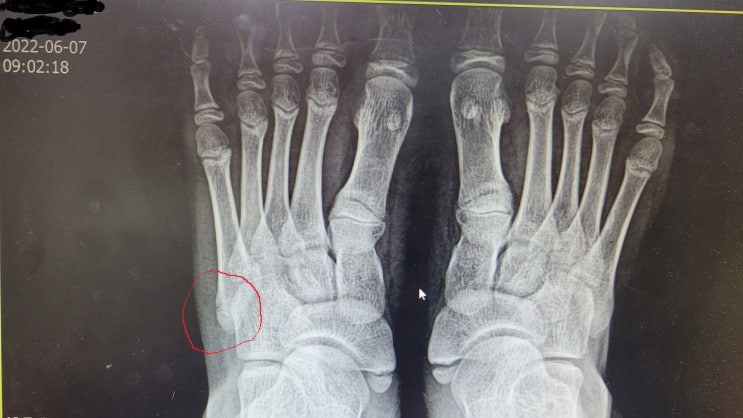

제주도 여행가기 전날 발바닥 골절된 아들 ㅠㅠ

안녕하세요? 작년에 드라마틱한 사건이 기억나서 적어봅니다. 2022년 6월 현충일을 포함해서 제주도에 여행...